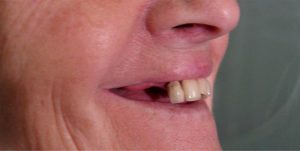

Fall Nr. 2: Vorläufiger herausnehmbarer Zahnersatz zum Wiedererlangen der Mundästhetik in drei bis fünf Tagen